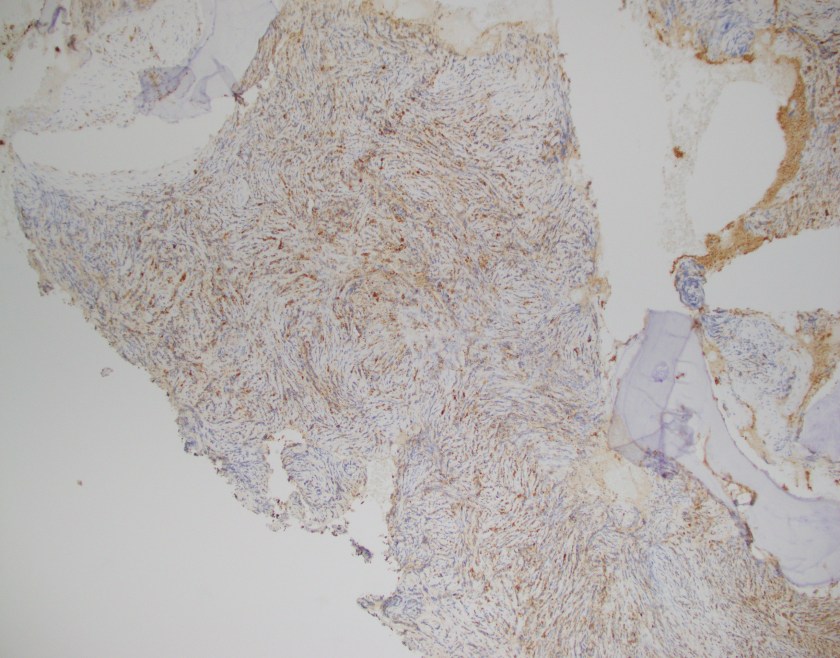

The CBC demonstrated severe anemia and mild leukopenia. The peripheral blood smear showed numerous acanthocytes and poikilocytosis shown below.

Acanthocytes, or spur cells, are spiculated red cells with a few projections of varying size and surface distribution that can be seen in a variety of clinical conditions including CGD with McLeod red cell phenotype. Other conditions include (but are not limited to) neuroacanthocytosis, malnutrition states, infantile pyknocytosis, (Lu) null Lutheran phenotype, hypothyroidism, myxedema, and Zieve syndrome. Acanthocytes should be distinguished from echinocytes, or burr cells, that also demonstrate multiple small projections but these are uniformly distributed on the red cell surface.

The prominent acanthocytosis seen in McLeod syndrome is thought to be due to an imbalance of the number of lipids in the inner layer relative to the outer layer. Related to this phenomenon is McLeod neuroacanthocytosis syndrome, a disorder with neurologic manifestations including movement disorders, cognitive alterations, and psychiatric symptoms. Although our patient did not exhibit these symptoms, McLeod neuroacanthocytosis syndrome is known to start in early to middle adulthood and the patient will need to be monitored for the onset of neurologic sequelae.